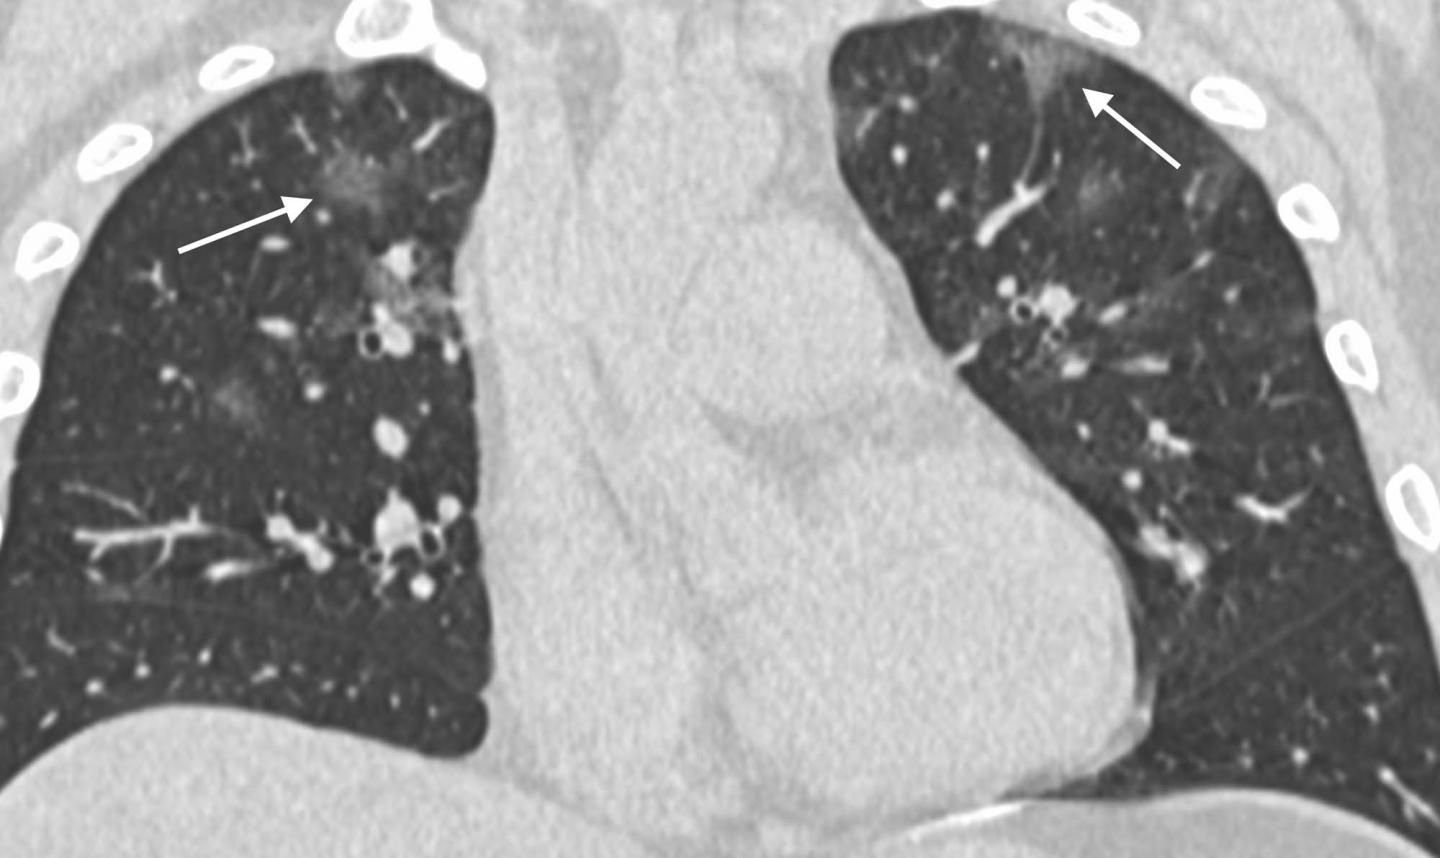

The analysis showed that 2019-nCoV typically manifests on CT with bilateral ground-glass and consolidative pulmonary opacities. Nodular opacities, crazy-paving pattern, and a peripheral distribution of disease may be additional features helpful in early diagnosis. The researchers also noted that lung cavitation, discrete pulmonary nodules, pleural effusions and lymphadenopathy are characteristically absent in cases of 2019-nCoV.

Follow-up imaging in seven of eight patients showed mild or moderate progression of disease as manifested by increasing extent and density of airspace opacities.

"Our patient population is unique from other published series on the Wuhan coronavirus in that three of our patients had normal initial chest CTs," he said. "One of these patients progressed three days later and developed a solitary nodular ground-glass lesion in the right lower lobe, indicating this pattern may represent the very first radiologically visible manifestation of disease in some patients infected with Wuhan coronavirus."